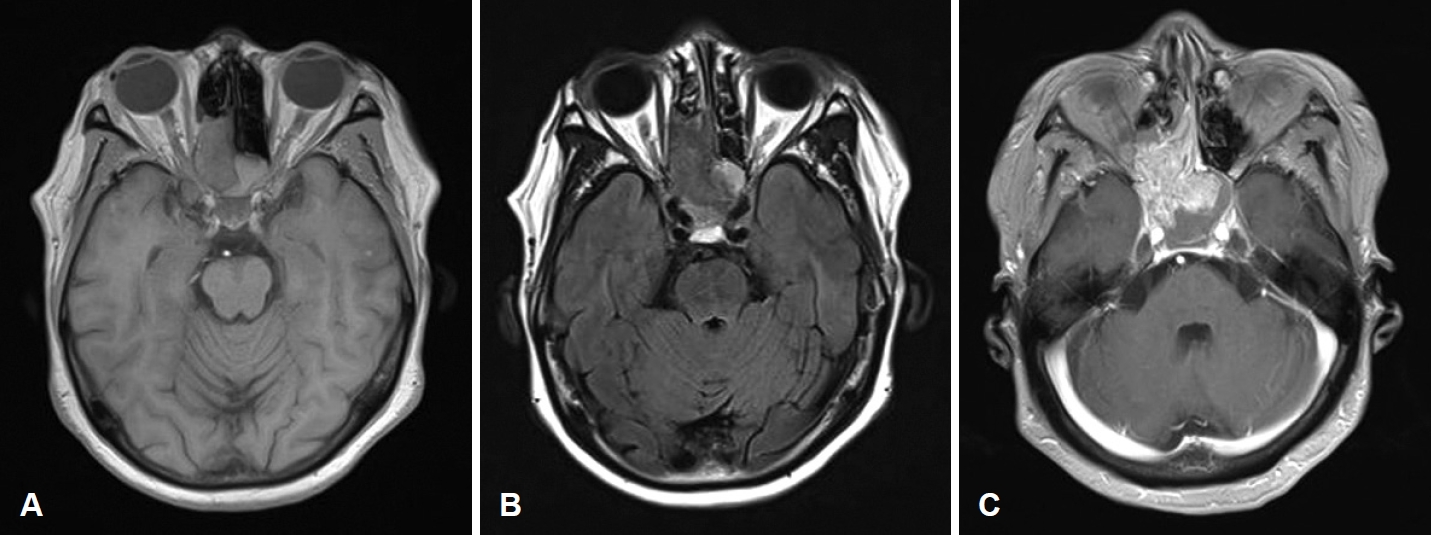

MRI scan findings were consistent with an intermediate signal on T1-weighted image (Fig. 2A), and heterogenous signal which includes presence of flow voids on T2-weighted image (Fig. 2B). Heterogenous enhancement was shown on contrast-enhanced T1-weighted image (Fig. 2C). Enhanced facial CT showed a 4 cm enhancing solid mass involving the right posterior nasal cavity, extending into the right ethmoid sinus and right sphenoid sinus, with evidence of bony erosion (Fig. 3). The left sphenoid sinus exhibited a non-enhancing mucoid density suggestive of sinusitis. Based on the imaging findings, the lesion was more consistent with an angiofibroma. Surgical treatment was decided accordingly.

Fig. 1.Endoscopic examination of right nasal cavity of the patient. A: Preoperative: a polypoid, whitish colored and solid mass found in the right nasal cavity, occupying between nasal septum and middle turbinate and extending to posterior nasal cavity. B: Postoperative 4 years: no residual mass or recurrence is found in the right sphenoid sinus. Fig. 2.Preoperative MRI images of the patient. A: T1-weighted image showed nasal cavity mass consistent with an intermediate signal. B: Heterogenous signal which includes presence of flow voids on T2-weighted image. C: Heterogenous enhancement was shown on contrast-enhanced T1-weighted image. Fig. 3.Preoperative enhanced facial CT images of the patient. A: Bony erosion of right lateral nasal wall by mass is shown in bone setting view. B: Both axial and coronal view show about 4 cm sized enhancing mass in right ethmoid sinus and sphenoid sinus. Fig. 4.Preoperative angiography. A: Through angiogram selected by right internal maxillary artery, hypervascular staining (red arrow) of right nasal cavity was shown. B: Hypervascular staining of right internal maxillary artery disappeared after embolization (blue arrow). Fig. 5.Microscopic features of permanent biopsy (hematoxylin and eosin stain, ×40). A: Sinonasal papilloma with inverted growth pattern. B: Various sizes of vascular spaces, ranging from dilated branching vessel to slit-like capillaries filled with fibrinous thrombin and edematous to collagenous stroma which indicates angiofibroma. REFERENCES2. Lisan Q, Laccourreye O, Bonfils P. Sinonasal inverted papilloma: from diagnosis to treatment. Eur Ann Otorhinolaryngol Head Neck Dis 2016;133(5):337-41.